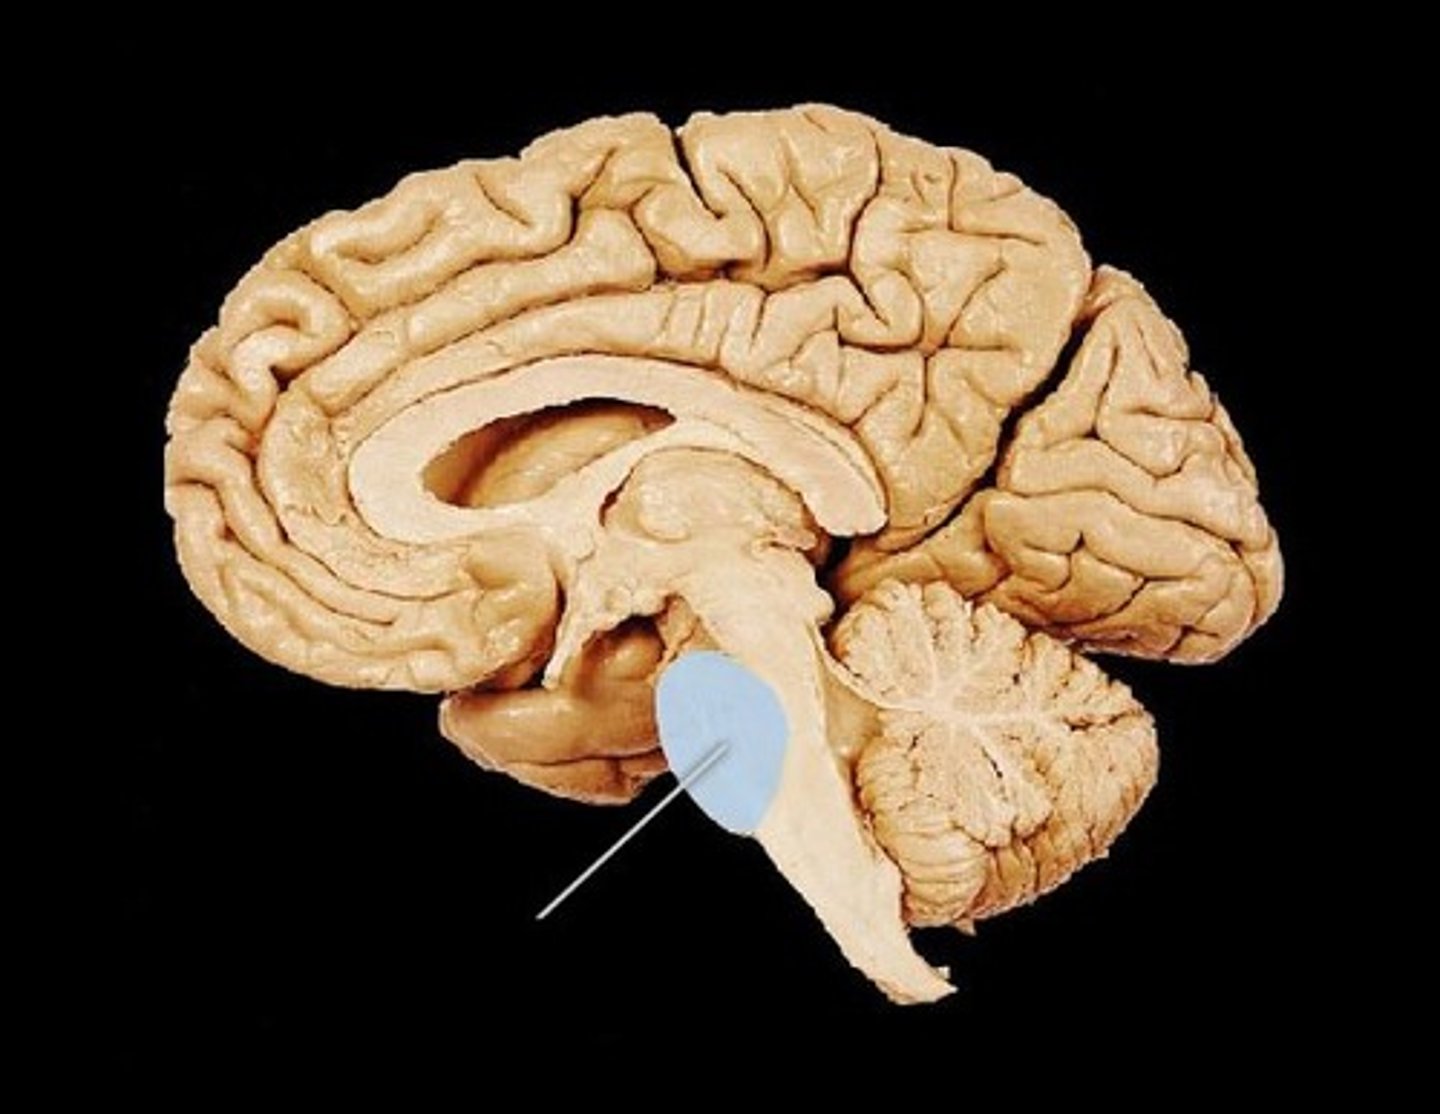

Pons

Part of the brain stem which connects parts of the nervous system, helps with movement. Ex: Coordinating the muscle movements required for facial expressions.